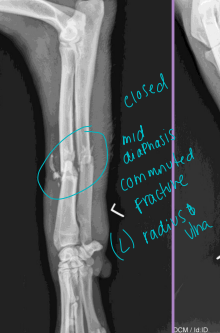

Describe the Fracture

Forces: Tension, compression, bending, torsion, shear

Pattern: Transverse, Oblique, Spiral, Comminuted

Diaphyseal Fractures

Tx: fxn alignment

Spiral: plate + screws, or IM pin + cerclage

pin sized to distal canal; normograde/retrograde; lateral → medial

Transverse: plate + screws, IM pin

Comminuted: plate + screws + IM pin, buttress, external fixator

Radius & Ulna Fractures

Considerations: No soft tissue envelope, weight-bearing, blood supply poor in small breeds, poor healing, Robert/modified jones bandage

Tx: rigid fixation, often only radius tx

Bone plate & screws (#1)